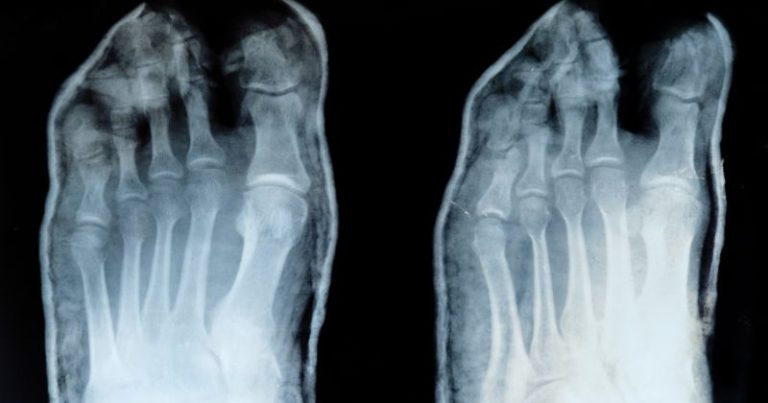

Protesi alla caviglia scan

Radiografia del calcagno: quando serve e cosa ci dice